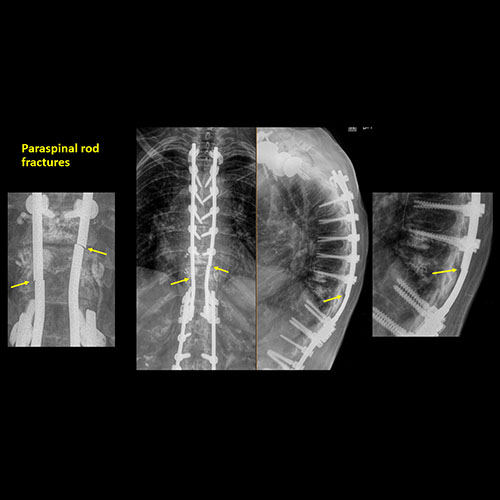

There is an abnormality or complication of post surgical hardware/device. |

N/A | NA |